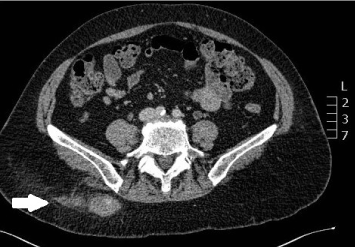

A 60 year old female presented with increasing right lower back pain and swelling at the site of a BMAT that was performed six weeks prior. The results of this BMAT were consistent with myelodysplastic syndrome. Her past medical history included large cell lung carcinoma 8 years prior that was treated with left lobectomy and chemotherapy. On presentation her platelet count was 30 ×109/L and her haemoglobin level was 92g/L. An ultrasound demonstrated a hypoechoic cavity measuring 37 × 20 × 23mm with internal vascular flow favouring a pseudoaneurysm. A computed tomography angiography (CTA) confirmed a pseudoaneurysm of a lumbar artery branch overlying the right iliac bone (Figures 1 and 2). It was planned to treat this with thrombin injection. In consultation with the haematology team, a unit of platelets was given which brought her platelet count to 50 × 109/L. During the procedure, the interventional radiologist found the pseudoaneurysm to be largely thrombosed and so it was treated with ultrasound guided compression alone with good immediate result. The patient was discharged and an ultrasound scan performed one week later showed a completely thrombosed pseudoaneurysm with no internal flow.

Figure 2. Computed tomography angiography: sagittal view of the lumbar artery pseudoaneurysm.